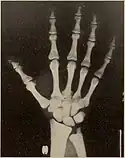

X-rays of the head and hand in pycnodysostosis, showing open fontanelle and shortened distal phalanges

Pycnodysostosis causes the bones to be abnormally dense; the last bones of the fingers (the distal phalanges) to be unusually short; and delays the normal closure of the connections (sutures) of the skull bones in infancy, so that the "soft spot" (fontanelle) on top of the head remains widely open.[9] Because of the bone denseness, those with the syndrome suffer from fractures.[7]